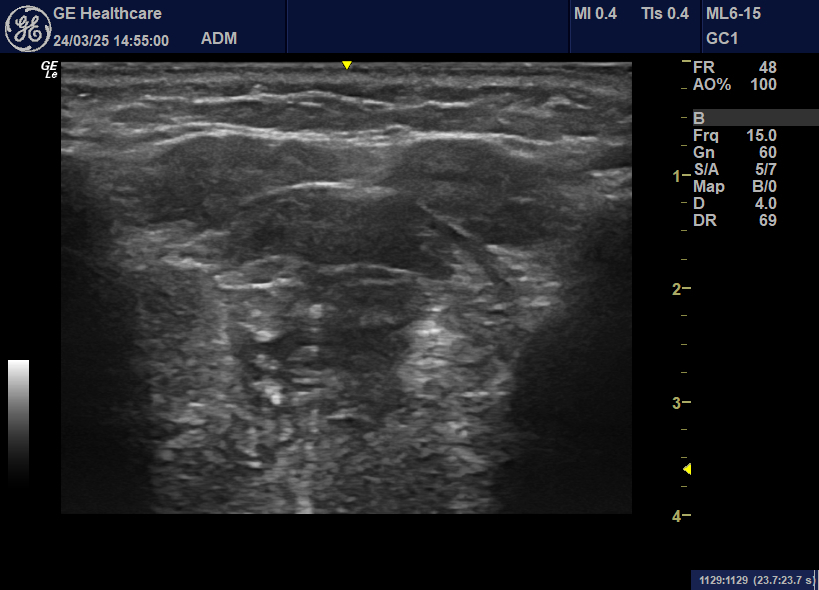

We are completing QMUS on 20 patients, pre-radiotherapy and at least 3 months post-radiotherapy. This involves assessment of the following muscles involved in speech and swallowing: submental muscles (left and right anterior belly digastric and geniohyoid), masticatory muscles (masseter and temporalis), and tongue muscles (longitudinal, transverse and genioglossus). We will use the ultrasound images to identify if we can a) identify the key muscles, b) measure the size of the muscles c) measure the structure and echogenicity (grayscale) of the muscles. We will also describe any differences between the two timepoints.